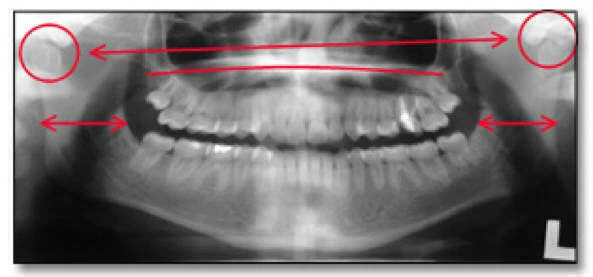

Đánh giá giải phẫu – Một số tính năng có thể được sử dụng để xác định độ chính xác về giải phẫu bao gồm:

- Các ống thần kinh có trên hình ảnh – Ở góc 60° và vùng ngang bằng.

- Hình ảnh vòm miệng và ảnh ma của vòm miệng phải ở trên đỉnh của răng hàm trên, chạy qua phần dưới của xoang hàm trên.

- Chiều rộng hàm phải rất cân xứng với nhau cả hai bên trái và phải.